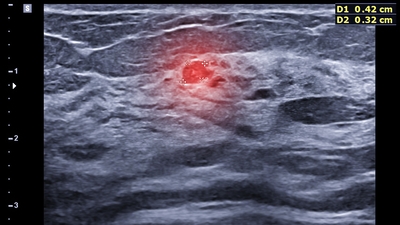

Hiçbir şikayet yaşamamasına rağmen erken teşhis sayesinde meme kanserine yakalandığını öğrenen Kapan, "Aile hekimim, Sincan Sağlıklı Hayat Merkezi (SHM) KETEM birimine randevu oluşturmayı teklif etmiş ancak acelem olduğu için sadece ilaç yazdırmaya geldiğimi söylemiştim. Randevuya pek sıcak bakmamama rağmen aile hekimim bu taramanın yapılmasının yararlarını ve gerekliliğini anlatarak randevumu oluşturdu. Sağlıklı Hayat Merkezine gittim ve hem mamografi çektirdim hem de serviks kanseri taraması için HPV numunesi verdim. Mamografi sonucum 'BIRADS 4 Şüpheli Bulgular (Hastaneye Sevk)' şeklinde geldi ve ileri teşhis merkezlerinden biri olan Abdurrahman Yurtaslan Onkoloji Eğitim ve Araştırma Hastanesine sevk edildim. Biyopsi sonucunda da 1. evre meme kanseri olduğum ortaya çıktı" dedi.